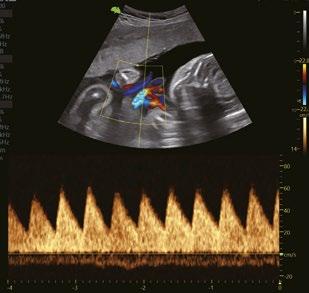

Nabelschnur PW

Mitral-Klappe PW